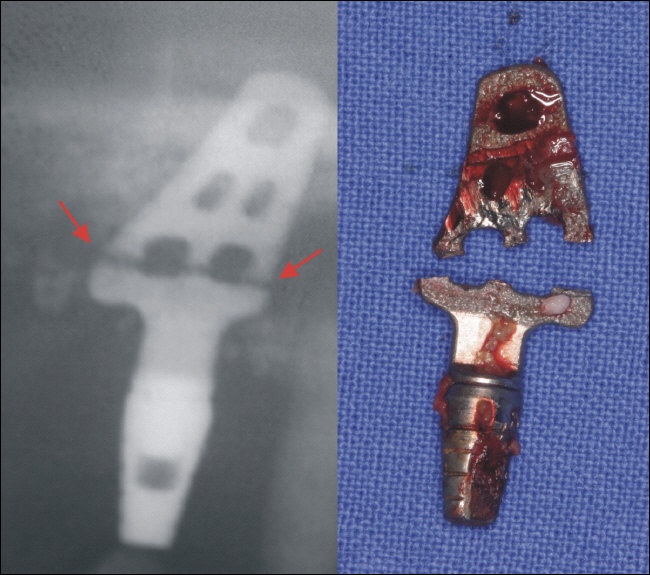

Einen neuen Weg zur optimalen Implantatform ging Linkow im Jahre 1968. Er wollte die Oberfläche des Implantates vergrößern und entwickelte so genannte Blattimplantate. Diese waren dünn wie ein Blatt, dafür aber viel größer ausgedehnt, weshalb sie auch als Extensionsimplantate bezeichnet werden. Sie hatten Löcher im Material in der Vorstellung, dass der Knochen in diese hindurchwachsen würde. Durch Ihre Form bedingt zeigten sich jedoch Materialschwächen bei Belastungen, was dazu führte, dass die Blattimplantate gerne brachen. Die Entfernung der Implantate führte darüber hinaus wegen der Größe zu ausgedehnten Kieferknochendefekten.

zum Vergrößern bitte auf das Bild klicken

Misserfolg durch ein gebrochenes Blattimplantat